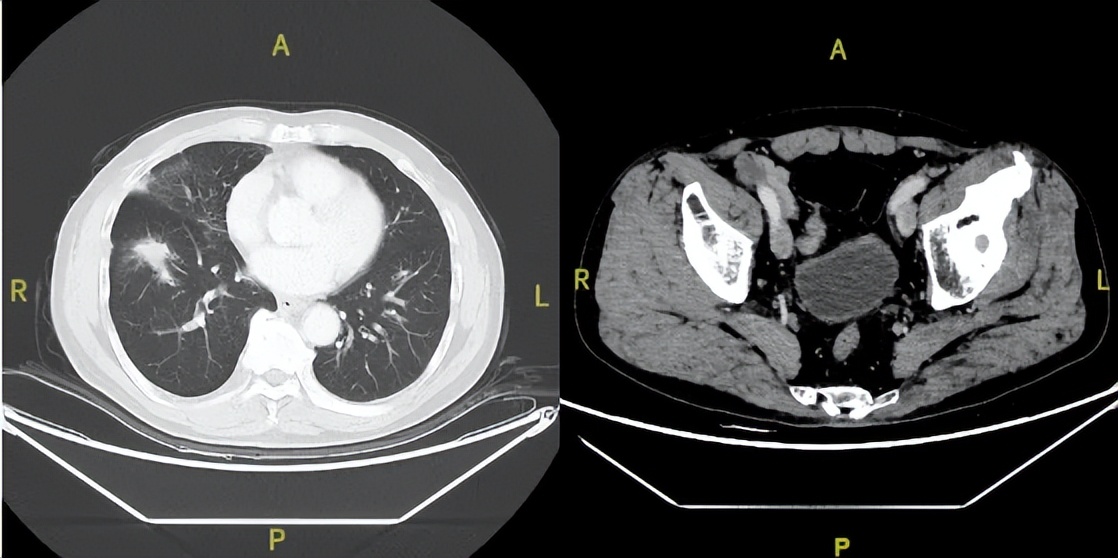

2025年9月24日

△治疗后不同随访时间的胸部及髋关节CT病灶变化

治疗第108周(C36)起:序贯呋喹替尼5mg单药治疗,持续维持PR,截至目前PFS已达38个月,仍在持续获益。